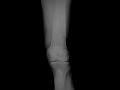

Bone infarcts

This is a 52 year old male who presents with knee and ankle pain. Frontal and lateral radiographs of the knee demonstrate intramedullary calcified lesions with a serpiginous pattern in the distal femur and proximal tibia. The appearance of the lesions in the femur and tibia has been described as having a "bone-within-bone" appearance. The radiographic appearance of the lesions by themselves can be seen with bone infarcts or enchondromas. The multifocality of these lesions is most consistent with bone infarcts. This patient was diagnosed with sickle cell disease as a teenager, a disease which commonly results in multifocal bone infarcts. Bone infarcts are associated with pain, and should not be mistaken for a malignant bone tumor.